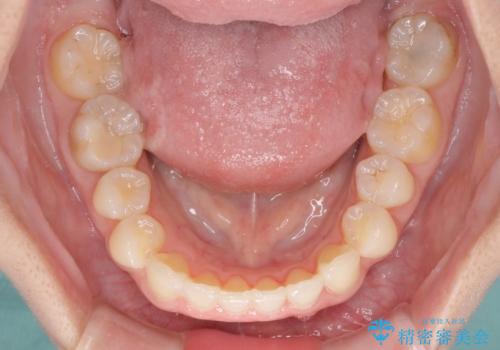

- 口元の深い咬み合わせ(ディープバイト)を気にして来院された患者様です。

インビザラインによる上下歯列の遠心移動(後方移動)により、口元のデコボコとディープバイトを改善することとしました。

下顎左右の犬歯とその後ろにある第一小臼歯、計4歯がシミュレーション通りに動かずディープバイトがなかなか改善されませんでした。

マウスピースの再製作を何度か行いましたがうまくいかないため、部分的にワイヤー矯正を併用することを提案しました。しかし、最も気になっていた前歯のデコボコはきれいに改善されたため、これ以上治療を希望されず、治療を終了することとしました。(今後気になった際には再開する予定です)